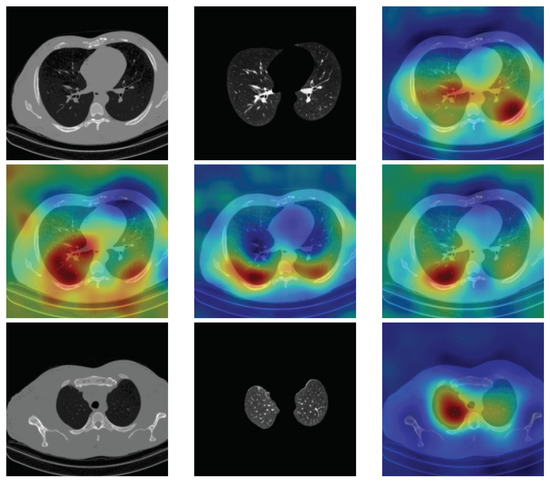

4.5. Heat Map

To have more intuition about the most important lung regions that the CNN architectures consider to classify the slice images, we used the randomized input sampling for explanations (RISE) approach [37]. Figure 13, Figure 14 and Figure 15 consist of two heat map examples of COVID-19, Cap, and normal cases, respectively. In the first example from Figure 13, we notice that despite the lung segmentation being not fully correct (it misses a considerable part of the infected region), the four CNN architectures gave more importance to the infected regions and to the lung regions in general. In the second example from Figure 13, we observe that the lung lobes were precisely segmented, and the heat maps of the four CNN architectures were well defined the infected regions, especially the Wide-Resnet-50 architecture. From both Cap examples in Figure 14, we notice that despite the lung segmentation missing considerable infected parts as well as the lung lobe regions, the heat maps of all CNN architectures give more importance to the infected region and to the lung lobes in general. This proves that the trained CNN architecture is able to define the regions of interest even when the lung lobes segmentation is not good. For the normal slice examples in Figure 15, the trained CNN architectures gave more importance to the lung lobes, especially the lower region, since the infection usually occurs there. The heat maps of COVID-19, Cap, and normal cases prove that the CNN architectures learned precisely where to look to identify the infection from the slice images.

Figure 15.

RISE heat map examples of normal slice image using the trained multi-tasks CNN architectures (ResneXt-50, Densenet-161, Inception-v3, and Wide-Resnet-50). The first example is shown in the first two rows, where the images represent the input slice image and segmented lung lobes results, followed by the heat maps of ResneXt-50, Densenet-161, Inception-v3, and Wide-Resnet-50, respectively. The second example is in rows 3 and 4.